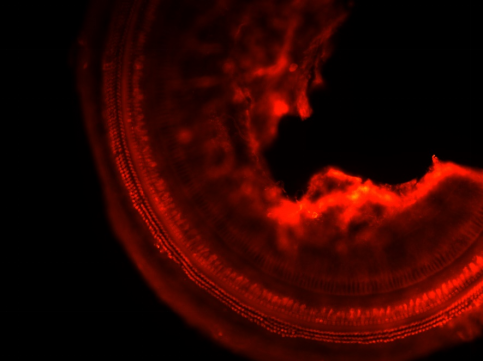

小鼠耳蜗是倒置荧光显微镜的一个典型应用场景。在这个应用中,需要观察细胞和组织的生物化学反应,以及药物对细胞的影响。倒置荧光显微镜可以清晰地观察小鼠耳蜗中的细胞和分子变化,帮助研究人员更好地理解疾病的本质,并为药物研发提供重要的线索。